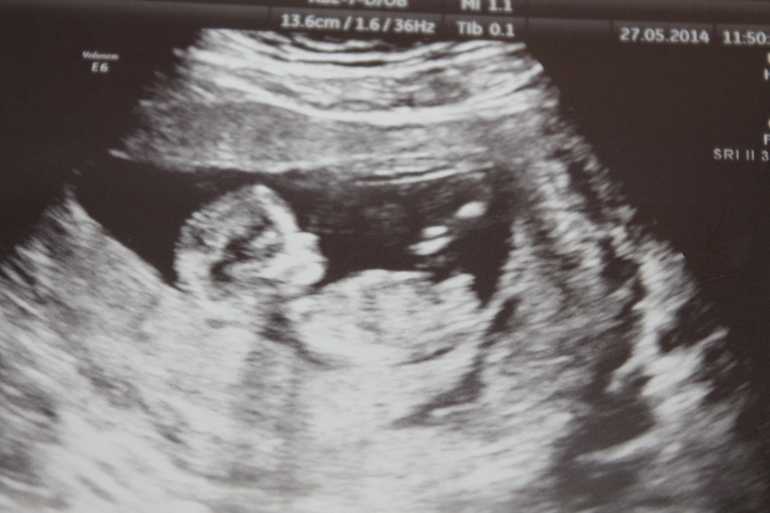

Какое же это чудо было наблюдать как кроха там прыгала, сосала пальчик, махала нам ручками... Врач который нас смотрел, просто замечательный (кому интересно Хачкурузов С.Г, Центр медицины плода на Сикейроса) все подробненько рассказывал и показывал, шутил с нами, я осталась очень довольна))) Еще нам с 90% уверенности сказали, что у нас будет ДЕВОЧКА, моей радости просто не было предела, а врач, все оставшееся время УЗИ так к ней и обращался - барышня :)

Как сказал доктор, просто замечательный ребенок, все показатели в норме, патологий никаких нет, развиваемся согласно сроку!

КТР- 48мм , что соответствует 11нед и 5 д. (прям один в один от М)

Сердечко - 166уд/мин.

ВП -1,3мм

Носовая косточка - норма; Допплерометрия трикуспидального клапана - норма; Допплерометрия венозного протока -норма.

ПДР - 11 декабря 2014г.

Ну и конечно же фото :)